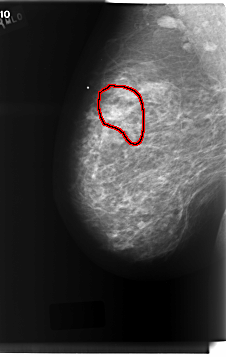

FILE: C_0213_1.RIGHT_MLO.OVERLAY

TOTAL_ABNORMALITIES 1

ABNORMALITY 1

LESION_TYPE CALCIFICATION TYPE PLEOMORPHIC DISTRIBUTION SEGMENTAL

ASSESSMENT 5

SUBTLETY 5

PATHOLOGY MALIGNANT

TOTAL_OUTLINES 1

BOUNDARY